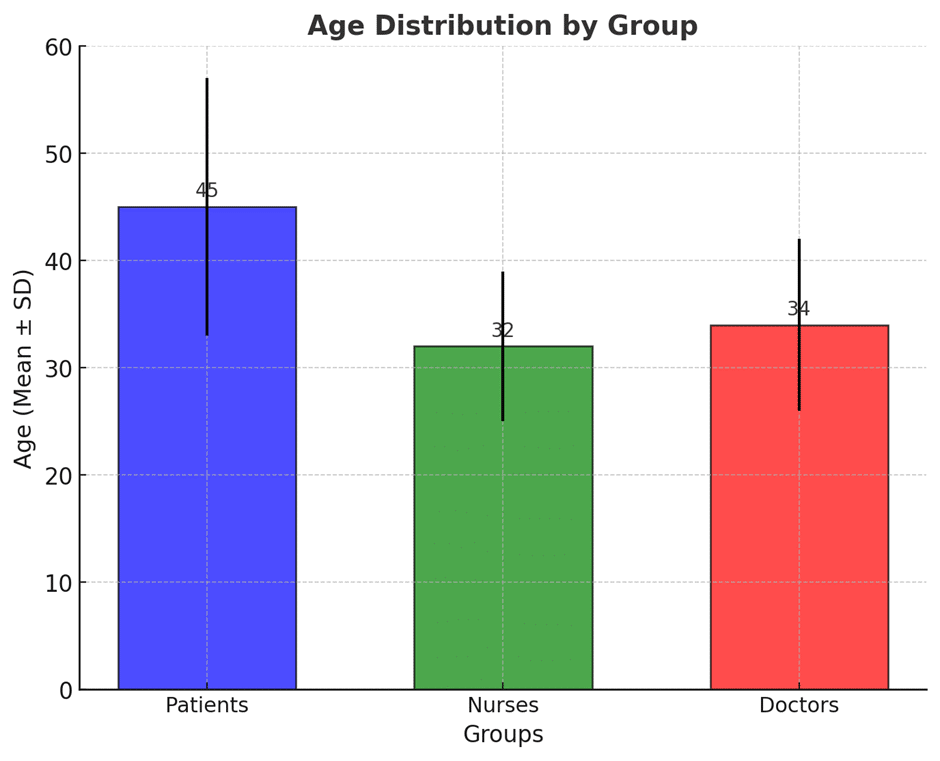

Teamwork and Therapeutic Communication Among Health Care Providers on Patient Satisfaction at Saidu Group of Teaching Hospital

Factors Influencing Career Choice Among Nursing Students in Swat, KPK, Pakistan